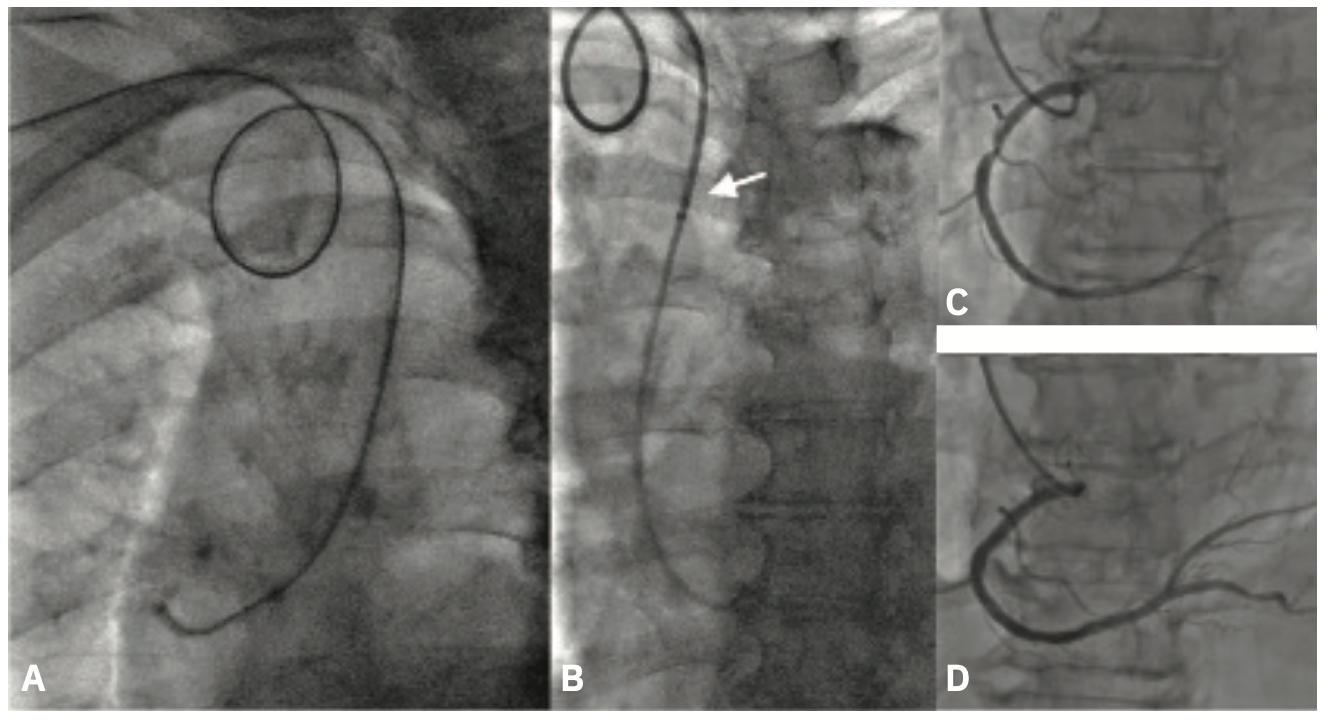

An 82-year-old gentleman with NYHA Class III dyspnea was referred for evaluation of a possible severe aortic stenosis (AS). An echocardiogram demonstrated possible severe AS with a mean gradient of 32 mmHg and an aortic valve area of 1.0 cm2 by continuity equation. The patient presented for elective cardiac catheterization to define his coronary anatomy and also for an invasive evaluation of the aortic stenosis severity. Prior to recent FDA recall, the Langston® Dual Lumen Catheter (Teleflex) had been our default to obtain simultaneous left ventricular and aortic pressures for assessment of aortic stenosis. Currently, a mother-and-child sheath and catheter arrangement using an 75 cm 6F R2P™ DESTINATION SLENDER™ Guiding Sheath and 4F pigtail catheter is the go-to technique for assessment of aortic stenosis via single arterial (radial) access in our lab.

Right radial access was obtained with a dedicated radial sheath. This was exchanged out for a 6F 75 cm R2P™ DESTINATION SLENDER™ Guiding Sheath to access the ascending aorta. The aortic valve was crossed with an .035-inch straight wire and a 4F pigtail catheter was placed. Dual lumen simultaneous pressure tracings were obtained from the 4F pigtail catheter in the left ventricle and 6F R2P™ DESTINATION SLENDER™ Guiding Sheath in the ascending aorta (Figure 3). This confirmed severe aortic stenosis with a mean gradient of 44 mmHg and an aortic valve area of 0.8 cm2.